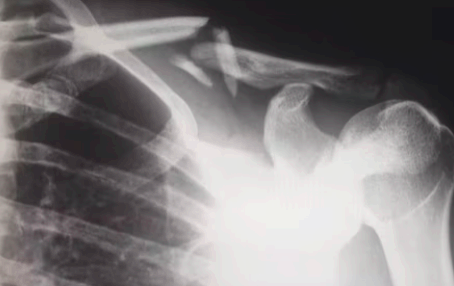

다음 어깨 회전근개파열 증상으로는 관절염과 탈구 증상입니다. 관절염의 경우에는 상완골두 즉 상완을 구성하는 뼈가 올라가 견봉과 맞닿으면서 뼈끼리 닿아서 생길 수 있습니다. 최악의 경우 파열이 왔는데 이것을 방치하면 탈구로도 이어질 수 있으니 이 부분은 특별히 조심해 주시는 것이 좋습니다.

어깨 회전근개파열 치료방법 수술이 불가피한 경우가 있는데요. 바로 증상을 방치해서 악화된 상태이거나 파열의 범위가 넓은 경우 이러한 경우에는 회전근개 봉합술과 같은 수술을 해야 할 수 있습니다.

이 수술법은 관절내시경을 이용한 수술방법으로 1cm 미만의 최소절개를 해서 특수기구를 삽입해서 파열된 회전근개를 봉합하는 수술입니다. 이 수술은 의사가 병변부위를 실시간 확인하면서 수술할 수 있기 때문에 주위 조직을 손상시키지 않을 수 있어서 안전합니다.